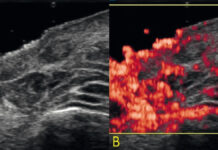

Użyteczność ultrasonografii wysokich częstotliwości w ocenie powikłań po zabiegach estetycznych wykonywanych w dolinie łez....

STRESZCZENIEDolina łez jest szczególnie wymagającą okolicą anatomiczną, której wygląd w dużym stopniu wpływa na estetykę twarzy. Zabiegi odmładzające wykonywane w tym obszarze cieszą się...